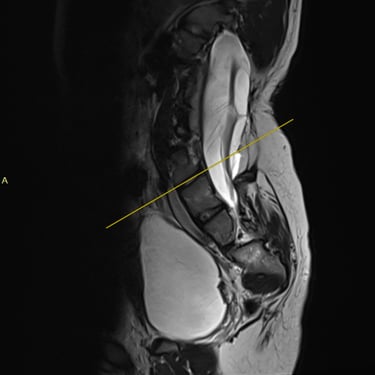

La médula anclada es una condición en la que la médula espinal queda fijada o traccionada anormalmente dentro del canal vertebral, generando síntomas como dolor lumbar, debilidad en las piernas, alteraciones sensitivas y disfunción urinaria. El tratamiento indicado es la liberación quirúrgica, un procedimiento microquirúrgico que busca desprender las adherencias y liberar la médula, permitiendo su movilidad normal. Se realiza con neuronavegación y monitoreo neurofisiológico para proteger las estructuras nerviosas. Esta cirugía, cuando se realiza oportunamente, detiene la progresión del daño neurológico y mejora la función motora y sensitiva del paciente.